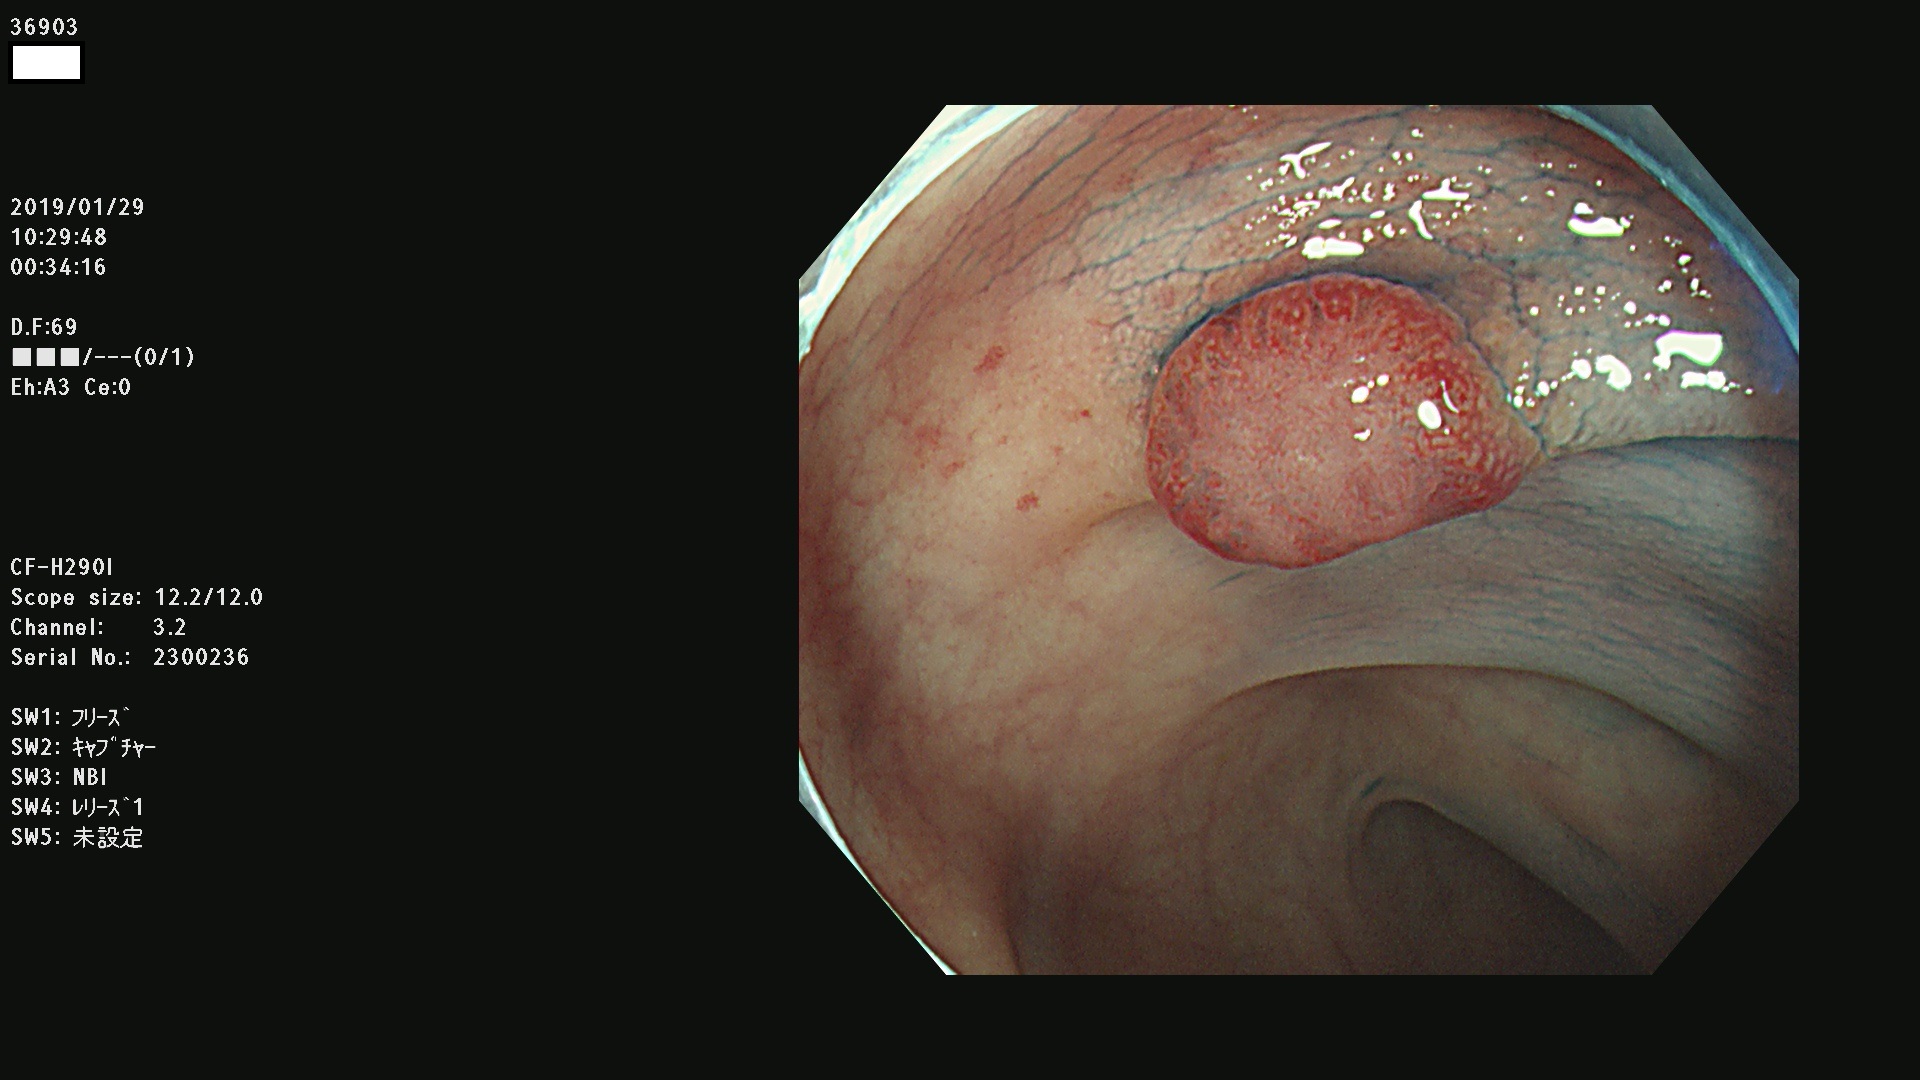

発見困難で危険性の高い平坦型病変(上記100名より抽出) ![]()